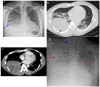

Coccidioidomycosis is a disease caused by soil fungi of the genus Coccidioides, divided genetically into Coccidioides immitis (California isolates) and Coccidioides posadasii (isolates outside California). Coccidioidomycosis is transmitted through the inhalation of fungal spores, arthroconidia, which can cause disease in susceptible mammalian hosts, including humans. Coccidioidomycosis is endemic to the western part of the United States of America, including the central valley of California, Arizona, New Mexico, and parts of western Texas. Cases have been reported in other regions in different states, and endemic pockets are present in these states. The incidence of reported cases of coccidioidomycosis has notably increased since it became reportable in 1995. Clinically, the infection ranges from asymptomatic to fatal disease due to pneumonia or disseminated states. The recognition of coccidioidomycosis can be challenging, as it frequently mimics bacterial community-acquired pneumonia. The diagnosis of coccidioidomycosis is frequently dependent on serologic testing, the results of which can take several days or longer to obtain. Coccidioidomycosis continues to present challenges for clinicians, and suspected cases can be easily missed. The challenges of coccidioidomycosis disease, from presentation to diagnosis to treatment, remain a hurdle for clinicians, and further research is needed to address these challenges.

Keywords: coccidioidomycosis; lung mass; pulmonary nodules; pyopneumothorax; valley fever.